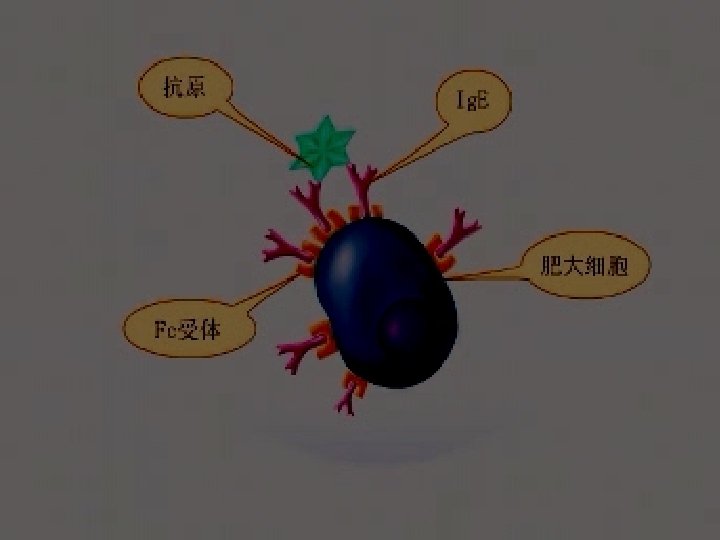

Pathology: Type allergy Allergic inflammation: Predominant T cells & eosinophilic cells infiltrate.